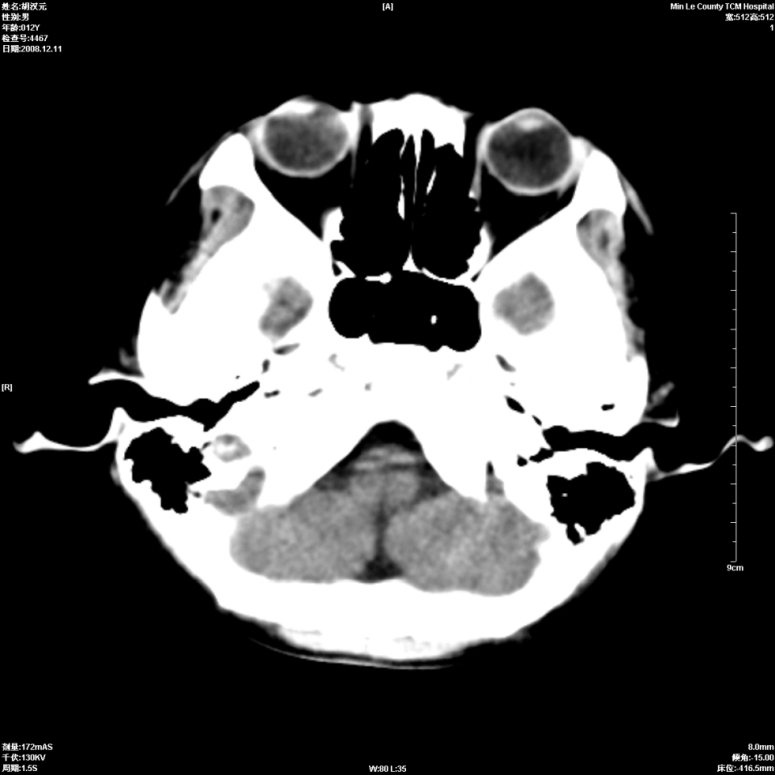

标题: PED1681:头疼发热约一周 [打印本页]

标题: PED1681:头疼发热约一周

颅脑未见确切异常。必要时进一步检查,如mri、脑脊液检查。

颅脑ct轴位平扫颅内未见明确异常;建议必要时复查或行进一步检查。

颅脑ct轴位平扫颅内未见明确异常;